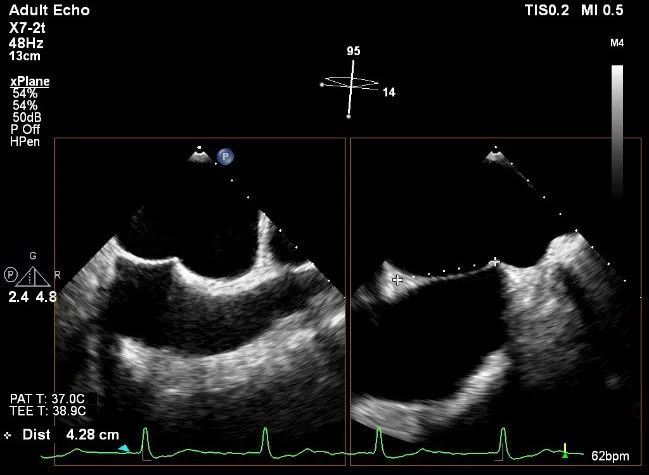

术中超声

确定房间隔穿刺点:靠后

2D视图下测量大鞘长度2cm

3D视图打开夹子

X-plane:下第夹子尝试捕获2区

X-plane:测量前叶长25mm,后叶长14.2mm

X-plane:计算前叶捕获长度8mm,后叶捕获长度7mm

3D视图下观察二尖瓣双孔形态

3D-color:残余少量返流